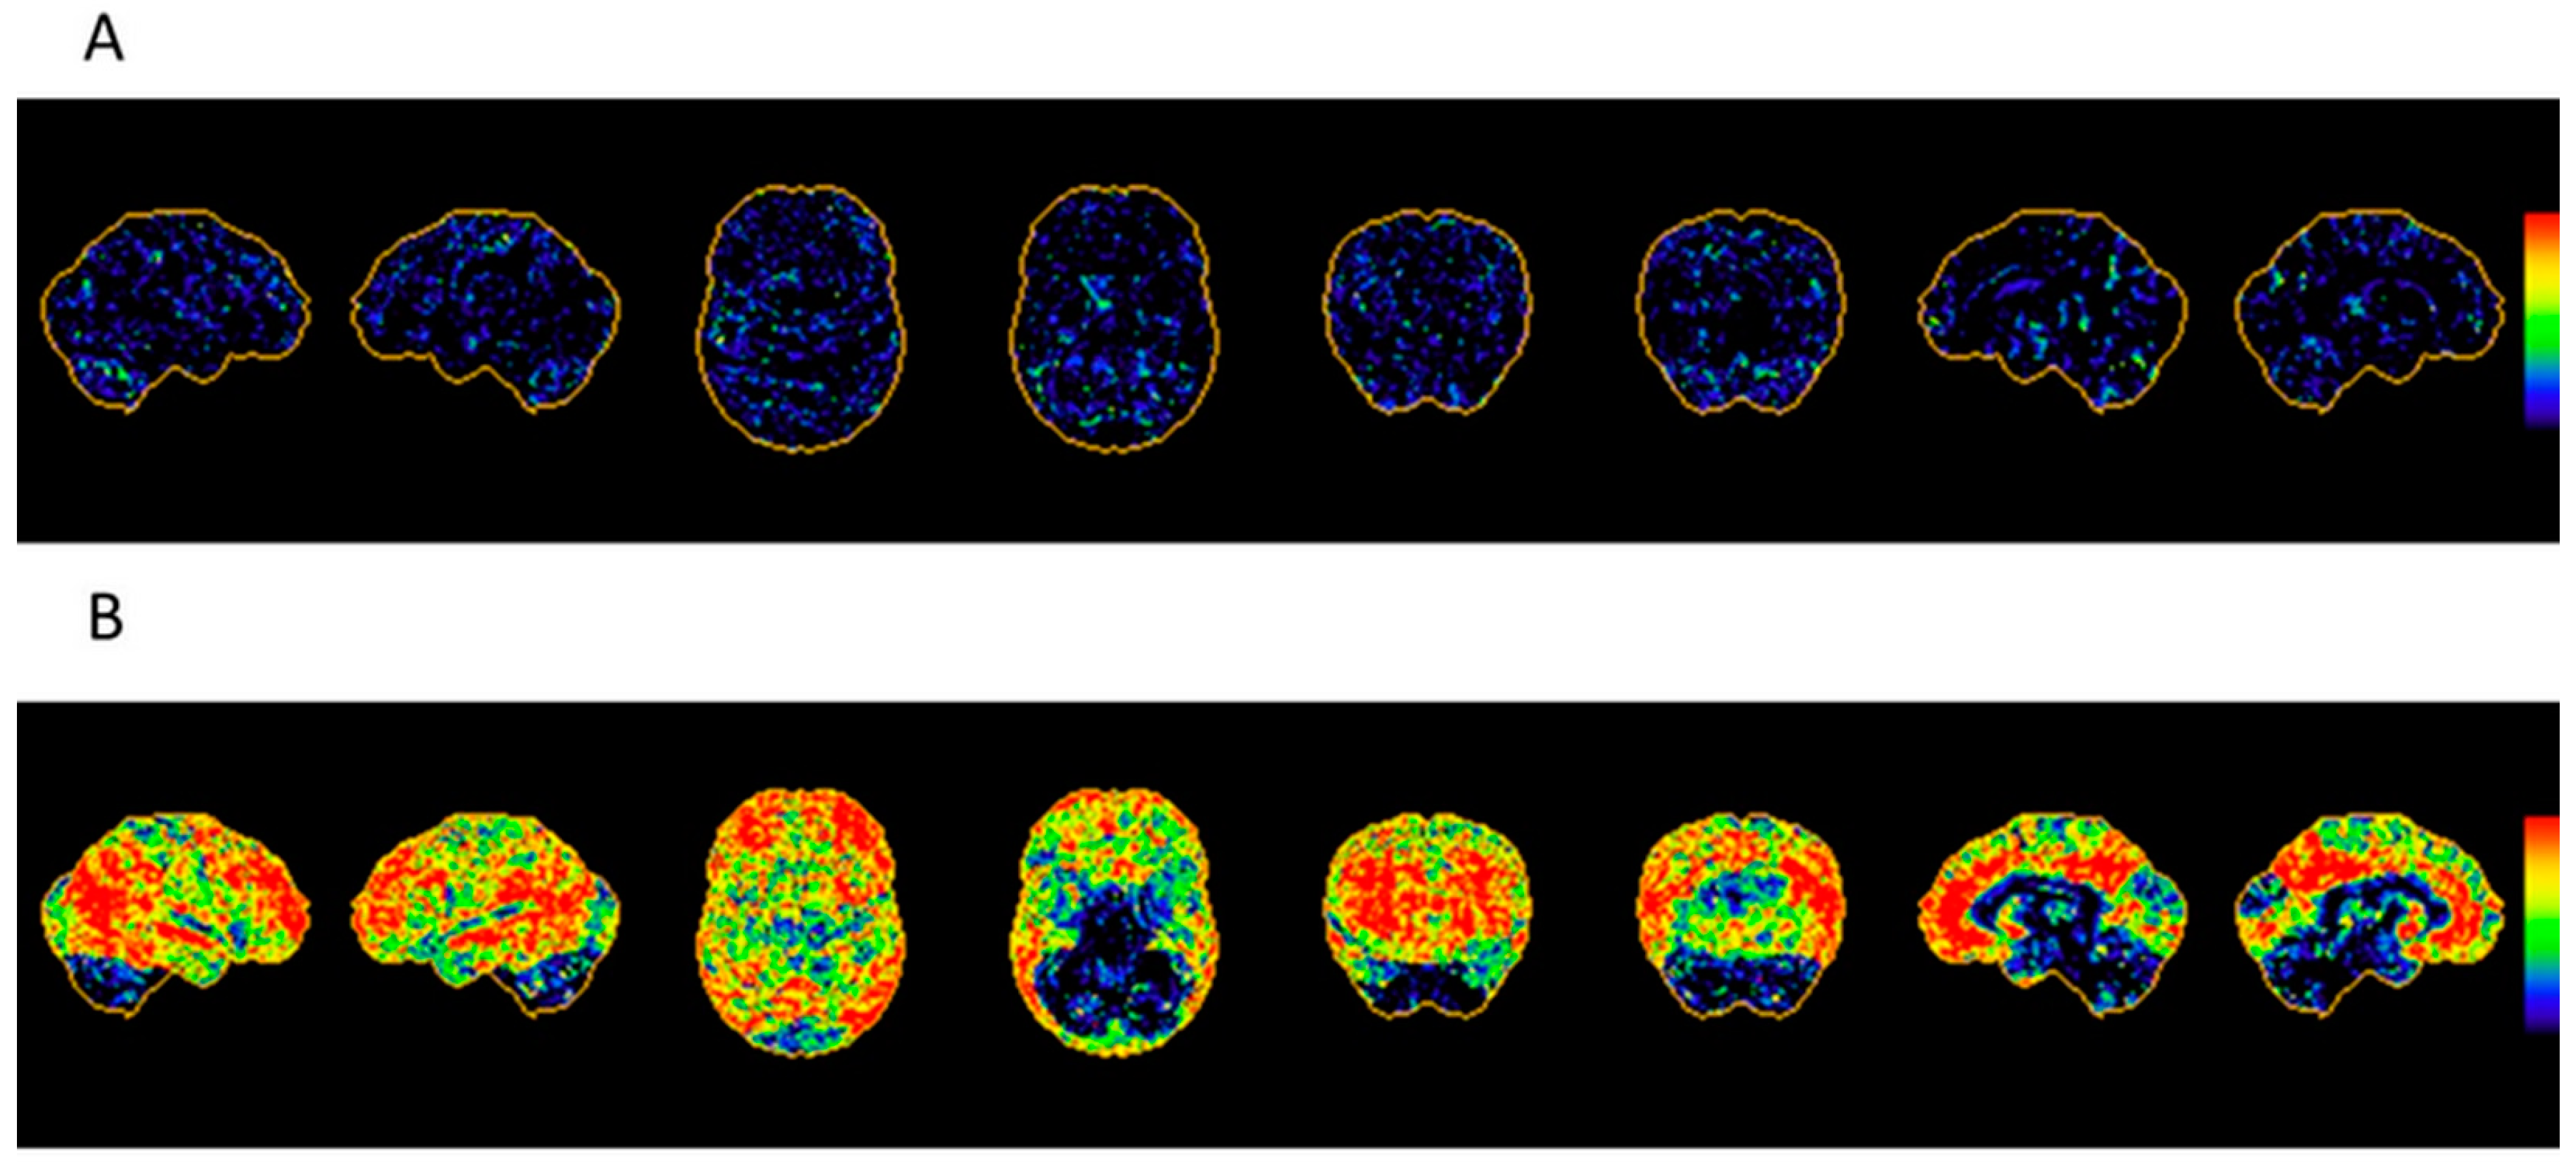

6.1.1. Imaging Data Display [45,50]

| Brain perfusion SPECT |

|

| FDG PET |

| Amyloid and Tau PET imaging |